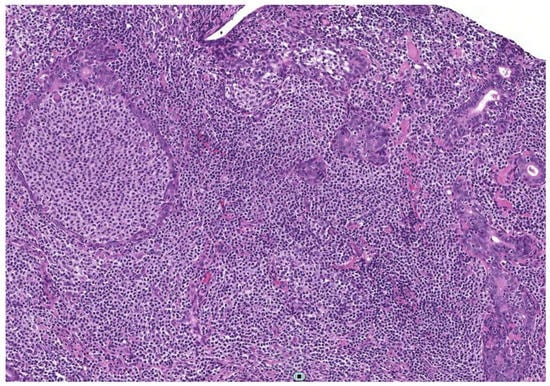

Figure 2.

Histological picture showing a marginal zone lymphoma of the MALT type in a parotid gland characterized by diffuse coalescence of centrocyte-like lymphocytes with lymphoepithelial lesions (H&E, 200×).

Benign and malignant lesions were easily discerned, and a rare entity, such as IgG4-related-disease, was detected. The US guide permitted the evaluation of specific and multiple targets, extending the site of sampling to unexplored areas, thus reducing the possibility of false-negative results. The five cases diagnosed as MALT lymphomas by histopathology showed features of suspected lymphoma on US evaluation (hypoechoic nodule with hypertrophic lymphoid structure, or a limited area with large and confluent hypoechoic lesions), similar to those described by Baer et al. []. Of note, MALT lymphoma was diagnosed only in the biopsy taken on the most suspicious focal lesion and not in the surrounding glandular parenchyma in one patient. This finding highlights the importance of a US-guided approach in performing a major SGs biopsy and that specific sonographic features might correlate with equally specific pathologic patterns. In the cohort of 13 controls who underwent open surgical biopsy in the same study, the procedure provided sufficient tissue for pathological evaluation in 12/13 patients, but was taken from a restricted glandular region (“safety zone”), which cannot effectively represent the whole disease affecting the gland.